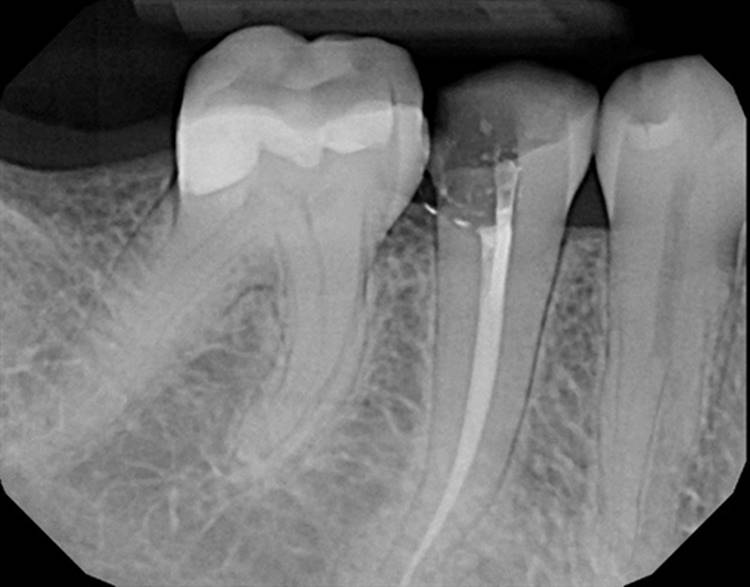

Forgive the sensor change from the first two cases to the last two. The good sensor broke and the back up isn’t as great.

EdgeFile® Cases